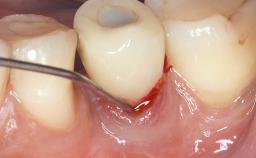

Treatment of Peri-Implant Mucositis at a Zirconia Implant